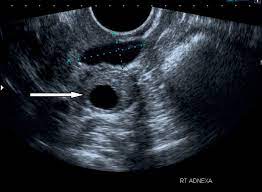

Sonographic Assessment Of Ovarian Cysts And Masses Chapter 8 Gynaecological Ultrasound Scanning from static.cambridge.org I was also diagnosed with diverticulosis following a ct a year before final diagnosis of stage 3 ovarian cancer. Can 19mm ovarian dermoid cyst be mistaken (misdiagnosed) with any another cysts? However, as women, this is something we need to be talking about. Malignant ovarian cysts are only seen in rare cases, with the benign being the most common of them all. A healthy ovary and one from a woman with pcos. Hi, my gyno told me that i had a dermoid cyst, even after my ca 125 test results were 2274. If you have a history of breast or ovarian cancer in your family, tell your ob/gyn so they can check for symptoms early on. They are often harmless and require no treatment.

Ovarian Cancer And Cysts What Is The Link from post.medicalnewstoday.com If there are clues that this mass could be cancer, you will be referred to a cancer surgeon (a gynecologic oncologist) for further examination and consultation. The ratio of cancers caused by dermoid cyst among malignant germ cell ovarian tumors is 2.9% (1, 2). It is a benign tumor that usually affects women of reproductive age (teens through forties). The dermoid ovarian cyst is sometimes called an ovarian neoplasm or dermoid cyst on the ovary. He doesn't think my reflux problem is related to my pelvic pain. Dermoid cysts are also known as mature teratomas. The cyst can also lead to a twisting of the ovary ( torsion ). The cancer surgeon can remove the mass, and if it is determined to be cancer, can also remove lymph nodes to see if the cancer has spread.

Ovarian cancer and cysts have similar symptoms and signs, for example, pain during intercourse, pelvic pain, and urinary problems. After pleading with one doctor to finally listen to her, she got a much more. Mature cystic teratomas, also called dermoid cysts, rarely undergo a malignant transformation, i.e. Yesturday i had keyhole surgery to remove what they thought was just a normal 6cm cyst on my right ovary. Ovarian cancer starts in the cells lining the ovaries. Every year, 7,000 women are diagnosed with ovarian cancer and 4,300 women lose their lives to it. Malignant ovarian cysts are only seen in rare cases, with the benign being the most common of them all. These benign cysts originate from germ or embryonic cells and thus contain different kinds of tissue such as cartilage, bone and skin. However, as women, this is something we need to be talking about. What is dermoid ovarian cyst? The largest type of ovarian cyst is called a cystadenoma. Her surgery was due to multiple painful complex cysts on her uterus. This is one of the main reasons why ovarian cancer is so difficult to detect at an early stage.

Ovarian Cysts Medical News Bulletin from medicalnewsbulletin.com Dermoid cysts are also known as mature teratomas. Ovarian cancer is misdiagnosed as cyst and ovarian cysts are often mistaken for ovarian cancer. Around 90% of ovarian cancers occur in women. The cancer surgeon can remove the mass, and if it is determined to be cancer, can also remove lymph nodes to see if the cancer has spread. They occur mostly in young women and are even found in children. Survey findings showed that doctors found it easy to mistaken symptoms such as abdominal or pelvic pain and bloating—the two most frequently cited symptoms of ovarian cancer—for other conditions, such as irritable bowel syndrome, urinary tract infections, acid reflux or stress. I am very worried and scared. Ovarian cysts of less than 1 centimeter (0.4 inches) in size are common in postmenopausal women, the vast majority of which will be benign.

February 2, 2016 at 1:10 pm. The mature teratoma is by far the most common ovarian germ cell tumor. Ovarian dermoid cysts, or teratomas, are. 1 doctor answer • 5 doctors weighed in share Ovarian cysts of less than 1 centimeter (0.4 inches) in size are common in postmenopausal women, the vast majority of which will be benign. This isn't the same as cause cancer; I was also diagnosed with diverticulosis following a ct a year before final diagnosis of stage 3 ovarian cancer. It is often called a dermoid cyst because its lining is made up of tissue similar to skin (dermis). They are often harmless and require no treatment. Malignant ovarian cysts are only seen in rare cases, with the benign being the most common of them all. A healthy ovary and one from a woman with pcos. Over the weekend i traveled to my hometown to support my mom while she underwent hysterectomy surgery. I kept complaining of a pain in my right side, about where i thought my appendix would be.